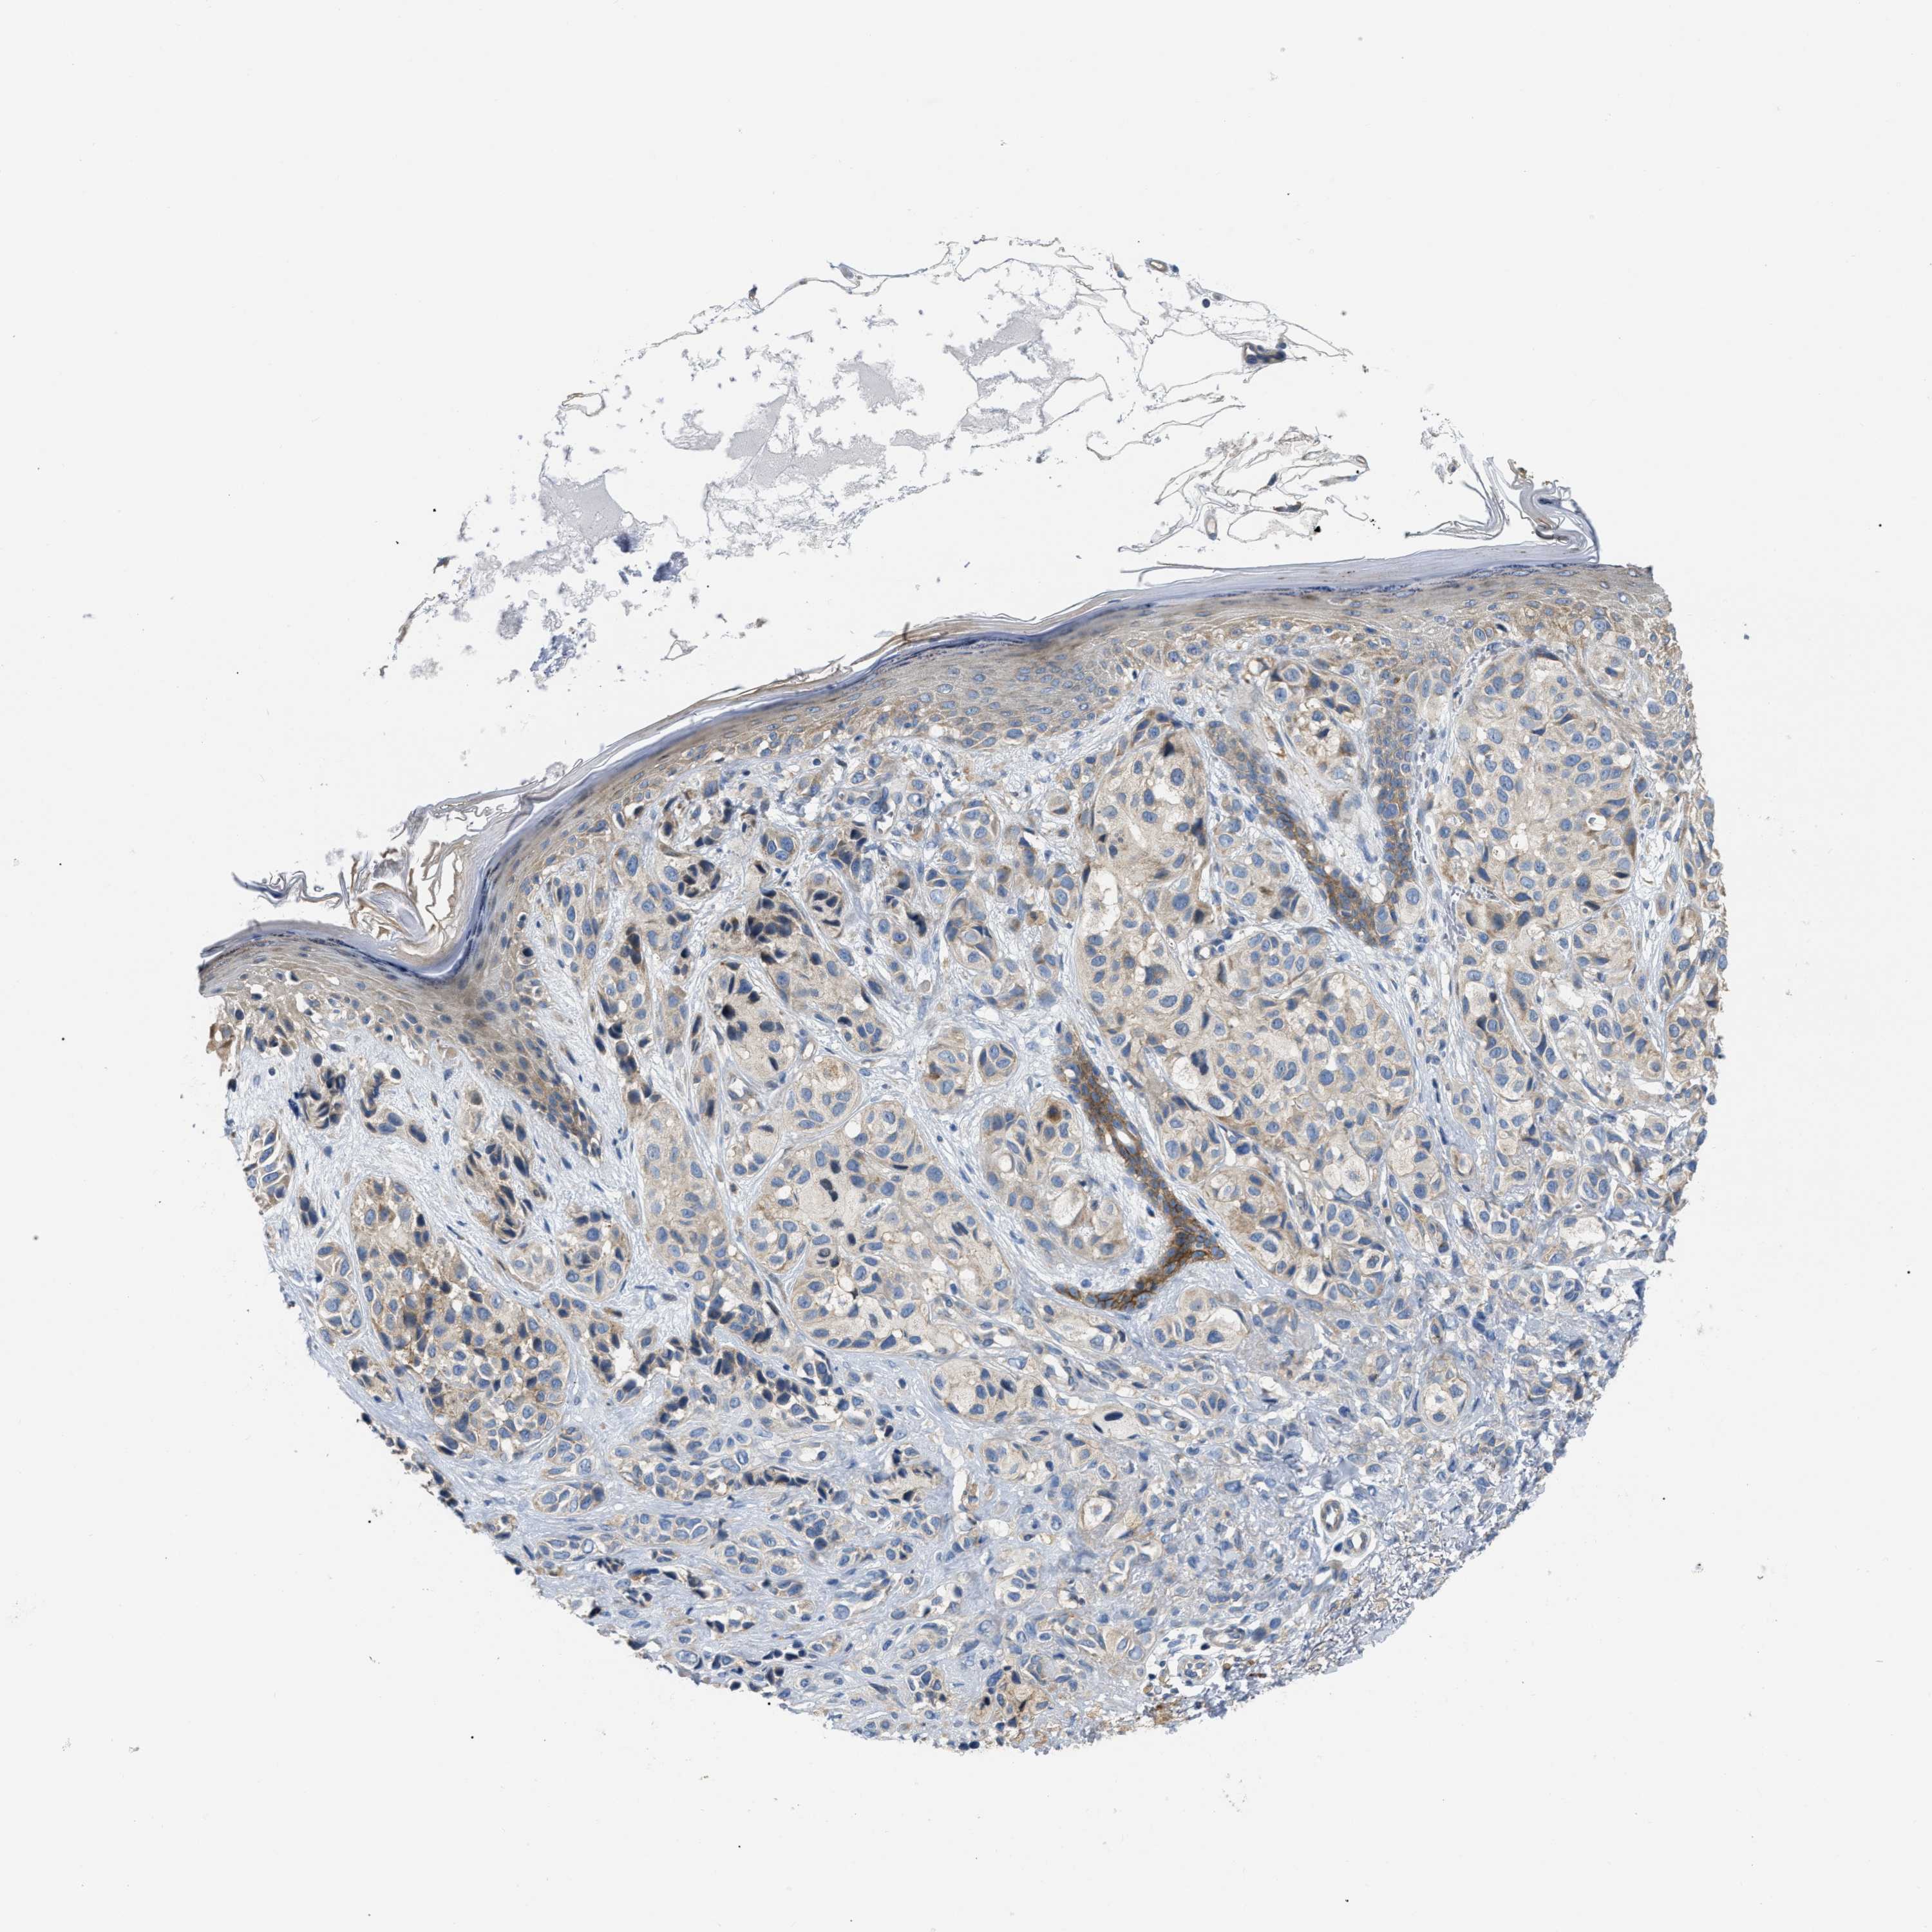

MELANOMA - Protein expressioni

A mouse-over function shows sample information and annotation data. Click on an image to view it in a full screen mode. Samples can be filtered based on level of antibody staining by selecting one or several of the following categories: high, medium, low and not detected. The assay and annotation is described here.

Note that samples used for immunohistochemistry by the Human Protein Atlas do not correspond to samples in the TCGA dataset.

Antibody stainingi

Antibody staining in the annotated cell types in the current human tissue is reported as not detected, low, medium, or high, based on conventional immunohistochemistry profiling in selected tissues. This score is based on the combination of the staining intensity and fraction of stained cells.

Each image is clickable and will lead to virtual microscopy that enables deeper exploration of all samples and also displays staining intensity scores, fraction scores and subcellular localization as well as patient and tissue information for each sample.

Antibody HPA018670

Antibody HPA019570

Staining

High

Medium

Low

Not detected

Intensity

Strong

Moderate

Weak

Negative

Quantity

>75%

75%-25%

<25%

None

Location

Nuclear

Cytoplasmic/membranous

Cytoplasmic/membranous,nuclear

Malignant melanoma, NOS

Malignant melanoma, Metastatic site